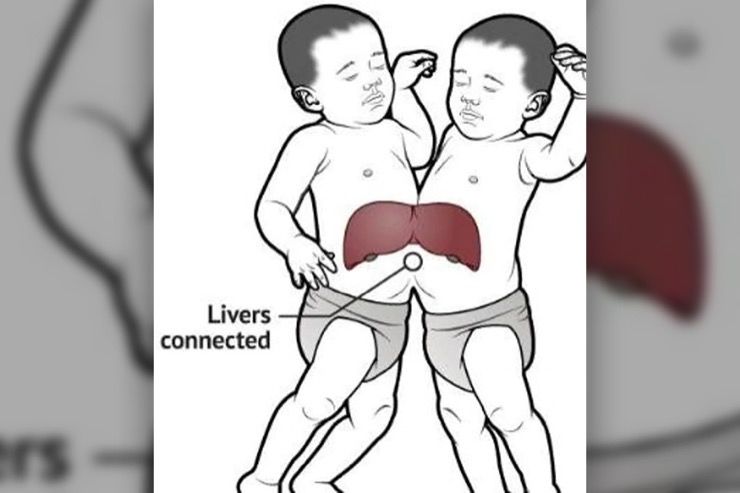

Total Separation

For Crameri, the procedure can be successful in separating the twins without leaving any “long-term legacies.” “We think they have joined liver which we can separate; we think they have joined bowel which we can separate; we don’t think they have major structures such as the heart or the lungs which are shared,” he said. “So it also means we have the opportunity to separate them without leaving them with long-term legacies, and I think that is important.”